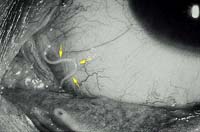

Khi bệnh diễn ra tại mắt thì mi mắt phù nề và ngứa, đôi lúc thấy giun dưới da và có thể sờ thấy được. Kết mạc phù, viêm kết mạc cấp, ngứa dữ dội, đôi khi thấy được giun chỉ màu vàng nhạt, mảnh dẻ, dài từ 3-6cm rất di động.